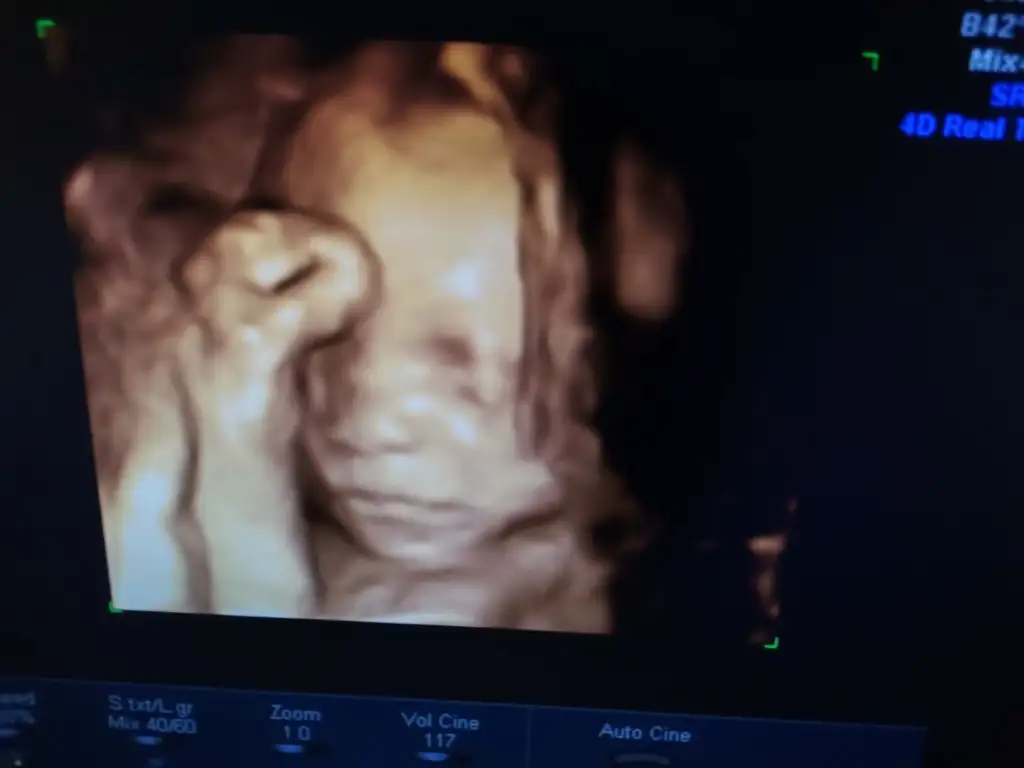

Valla minnoş içimi rahatlattı bir tek işte o kordon ne olur diye aklımda o kadar anca bu kadar elini çekti

Amanın aman ne tatlış bu poncik buruna bak yaa yerim..

Ah yaramaz kız sen kordonunu nasıl doladın şimdiden yaaa.. Canim sorun olmuyor korkma.. Benim ilk kizda dolanmisti bisicik olmadi düzenli kontrolune git ama